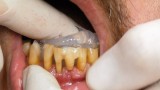

Jedną z popularniejszych metod stabilizacji zębów rozchwianych jest ich szynowanie. Metoda ta, wspierająca inne metody leczenia, jest powszechnie stosowana. Jednym z najnowocześniejszych materiałów wykorzystywanych w stomatologii do szynowania zębów jest taśma poliaramidowa. W opisanym przypadku autorzy pracy przedstawiają sposób uproszczenia całej procedury i ograniczenia ryzyka popełnienia błędu, szczególnie w sytuacji całkowitej utraty zęba. Uzyskano to dzięki zastosowaniu indeksu wykonanego z przezroczystego silikonu.

One of the more popular methods of stabilising loose teeth is to splint them. This method, aiding other methods of treatment, is generally used. One of the most modern materials used in dentistry for splinting teeth, is polyamide tape. In the case described the authors show how to simplify the whole procedure and limit the risk of making a mistake, particularly in the situation of total loss of one tooth. This was achieved thanks to the use of an index made out of transparent silicone.